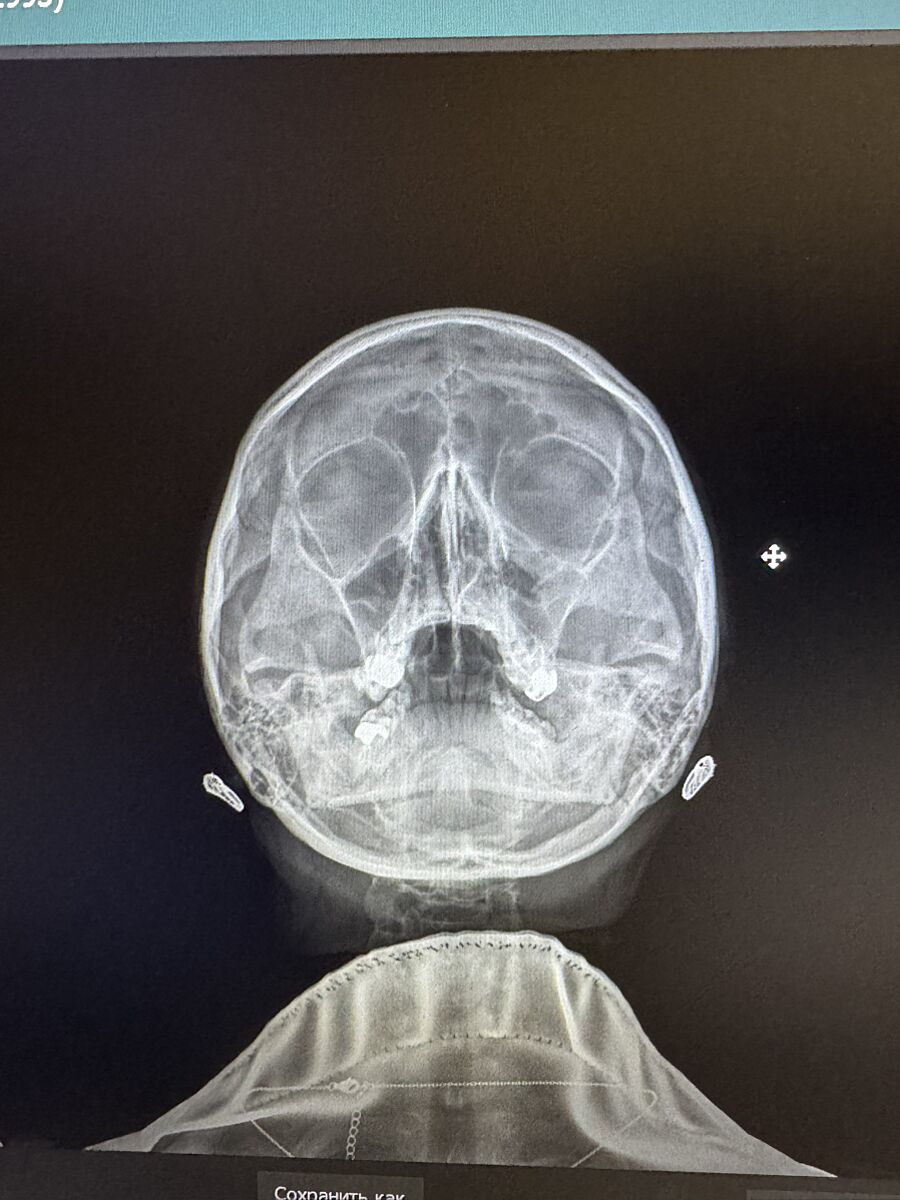

Тут є гайморит?

Врач каже нема гною, але по рентгену гайморит. Мені здається справа оте світле і є гній..хіба ні?

Оця фігня біла, у пазусі))в другій такого нема. Світле в пазухах це гній зазвичай...

Это может быть воспаление или экксудат ( обычная слизь) Что вам выписали?